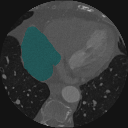

To bridge the methodological gaps when only small-scale partially labeled data is available, we propose a simple yet efficient framework Vicinal Labels Under Uncertainty (VLUU) by exploring the statistical similarity of human structures (e.g. shape, size, location) among different patients. See Fig. 1 for an illustration of such a similarity. The proposed framework is motivated by vicinal risk minimization (VRM) [11], where the fully labeled vicinal examples are generated by linearly combining randomly sampled partial labels with a weight randomly sampled from a Dirichlet distribution. These vicinal examples allow us to transform the partially supervised problem into a fully supervised one. That is to say, we can utilize any existing supervised segmentation networks and loss functions to solve partially supervised problems. The generated vicinal labels contain uncertainty regions where classes of interest could potentially overlap. We utilize these uncertainties in the training process to improve the robustness of DL models.

In standard adversarial training, the segmentation network and the discriminator play a zero-sum game. The discriminator is trained to discriminate the prediction masks produced by the segmentation network from the ground truth masks. Meanwhile, the segmentation network is trained to confuse the discriminator by producing realistic prediction masks. Adversarial training benefits from the human structure similarity as it makes the unknown true label distributions easier to be caught by the discriminator than for general objects [38]. In other words, there is smaller instance-wise variation in the size, shape, and location of human organs (or structures), as shown in Fig. 1, than for general objects.